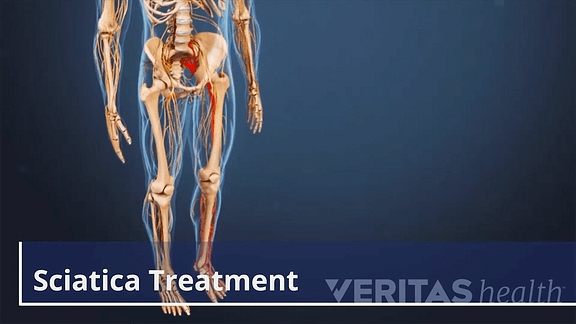

Download Sciatic nerve pain pictures